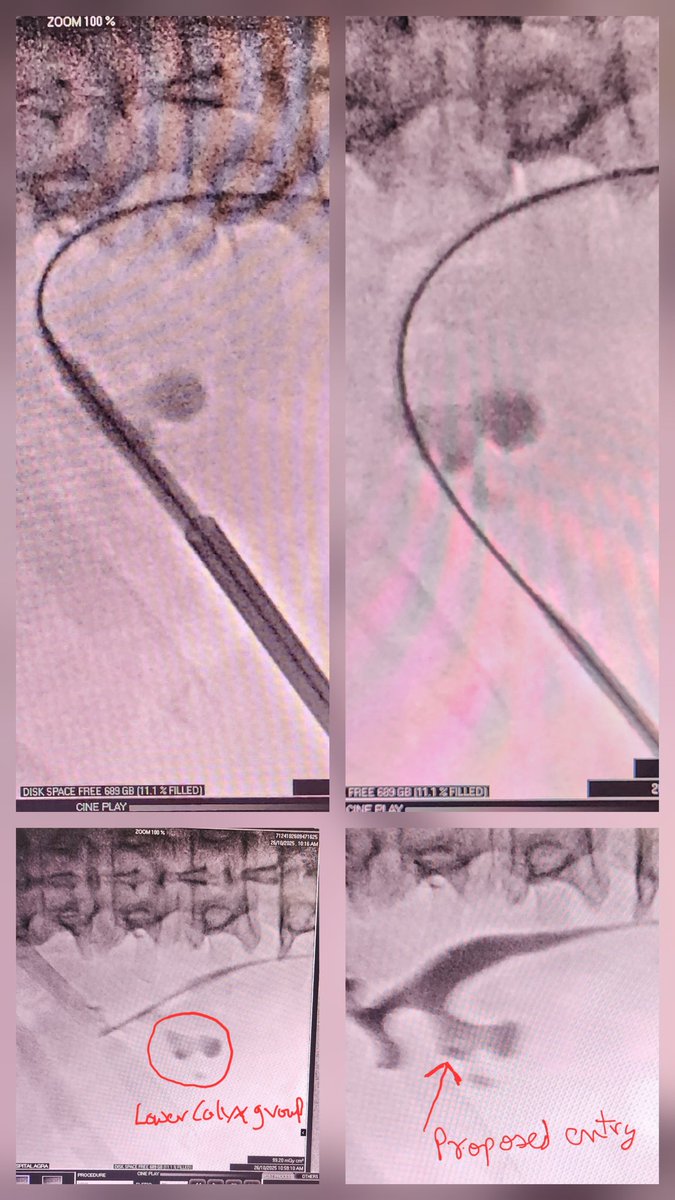

Suction assisted MiniPCNL. partial Staghorn LK Lower Calyx. 3D CT recon helps select ideal calyx entry for complete clearance. 25 min job. @endouro @endouroacademy @sbinhamrii @DocGauhar @amy_krambeck @DrParimalGharia @UroZedman @TFL_URO_APIS @Endo_Society